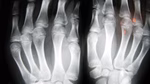

Artritis predstavlja jedan od glavnih krivaca za oteklinu zgloba. Kod reumatoidnog artritisa, imunološki sustav napada zdrave zglobove, što dovodi do kronične upale i otekline. Osteoartritis, s druge strane, nastaje zbog habanja hrskavice što rezultira upalom i nakupljanjem tekućine.

Ozljede poput uganuća, prijeloma ili udarca mogu izazvati akutnu oteklinu. Kada se zglob ozlijedi, tijelo šalje više krvi u to područje kako bi pokrenulo proces zacjeljivanja, što često rezultira vidljivom oteklinom.